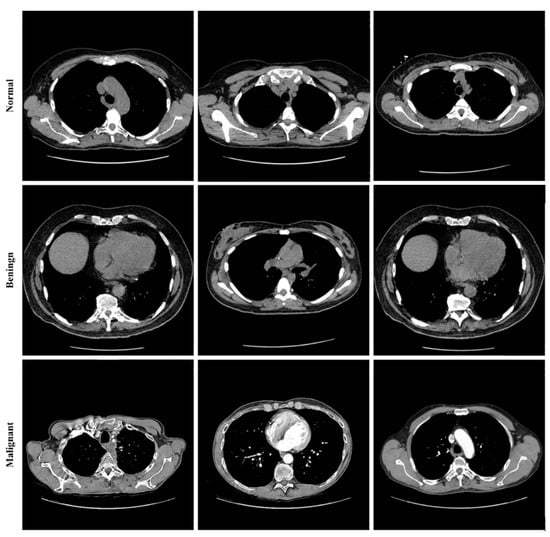

Lung cancer categorization may use a wide variety of currently accessible datasets. Lung Image Database Consortium Image Collection (LIDC-IDRI) [], Luna16 [], and NDSB3 (Neural Data Standardization Board, Version 3), were some of the datasets available []. It is possible to acquire images, analyze them, segment them, extract features from them, and classify them all with the help of a CAD system. For a CAD system to be constructed, it is necessary first to pre-process the datasets used in the project. This study used data from the LIDC-IDRI []. There were 910 photos utilized; 250, 320, 320 as normal, benign, and malignant, respectively. The RGB pictures were 512 pixels by 512 pixels in size. Lung cancer screening and diagnosing thoracic CT images with identified lesions made up the LIDC-IDRI. This dataset was compiled by the combined efforts of eight medical imaging firms and seven academic institutions. The data collection was initially stored in the format for Digital Imaging and Communications in Medicine (DICOM). An intermediate dataset was created by down sampling the original data and saving it in “jpeg” format. Denoising the dataset as part of the pre-processing step allowed us to obtain even better results. Figure 8 shows some images from the dataset.

Figure 8.

Sample images from the LIDC-IDRI dataset.